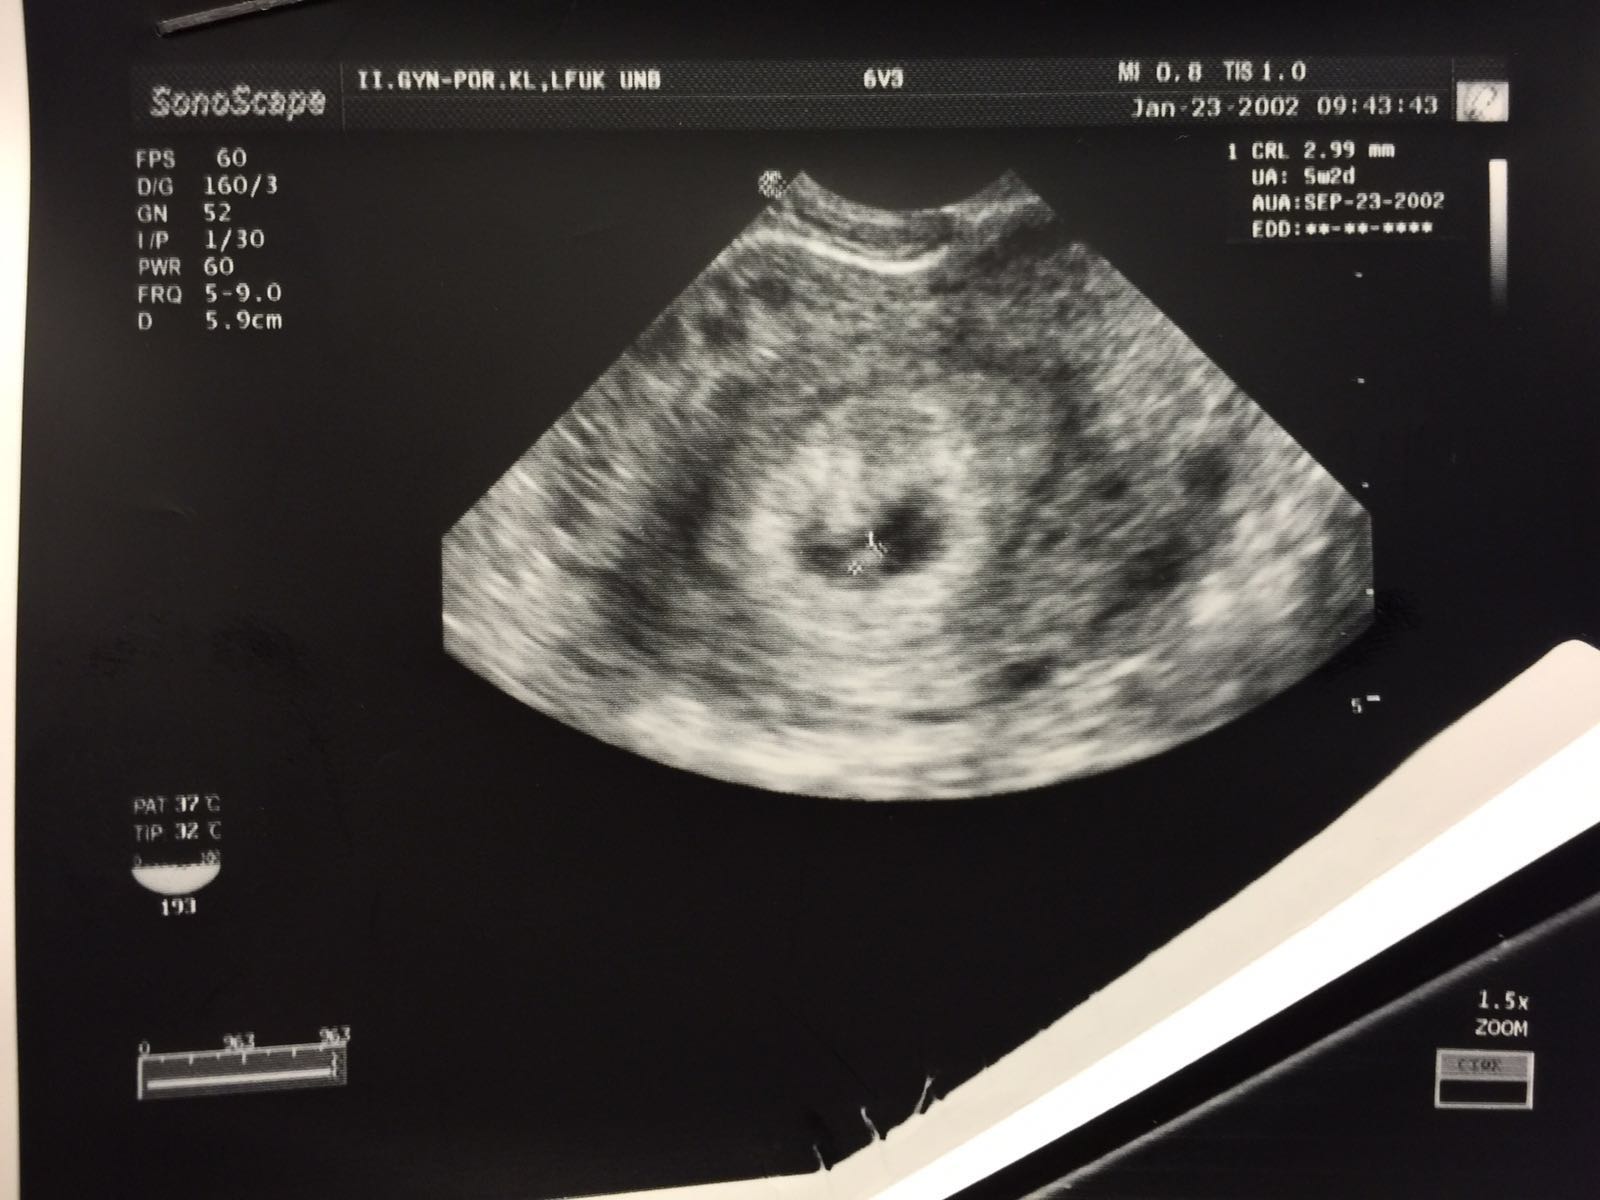

Dnes po KET 🙂

@meli8412 toto je zo soboty, zajtra idem opat na kontrolu